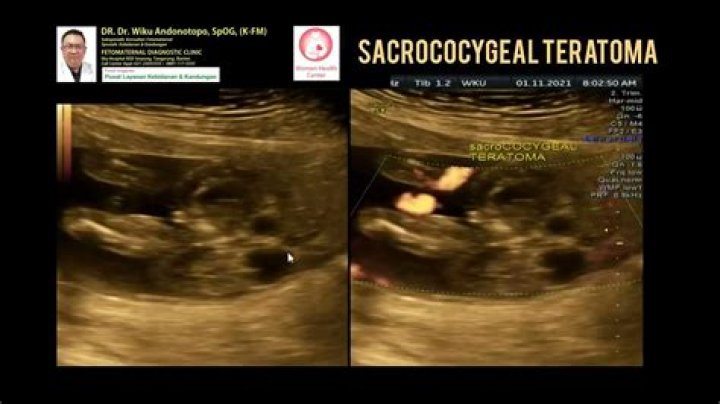

Is a sacrococcygeal teratoma a twin?

Unlike other neoplasias, sacrococcygeal teratomas are more common in twins than in singletons. 4 This report documents the presence and long-term follow-up of a sacrococcygeal teratoma in one twin discovered in the second trimester during routine obstetric ultrasound examination.

What is fetal sacrococcygeal teratoma?

A sacrococcygeal teratoma / SCT is a tumor that develops in a baby in utero. It appears in the lower back and buttocks of a baby at the base of the tailbone (coccyx). Some tumors are diagnosed in utero, others at birth. Sacrococcygeal teratomas / SCTs are rare, occurring in about one in 35,000-40,000 births.

How is sacrococcygeal teratoma diagnosed?

How is sacrococcygeal teratoma diagnosed? A sacrococcygeal tumor is usually diagnosed during pregnancy by a highly specialized prenatal ultrasound. You may be referred to a doctor who specializes in this kind of an ultrasound if the levels of alpha-fetoprotein (AFP) in your blood are high.